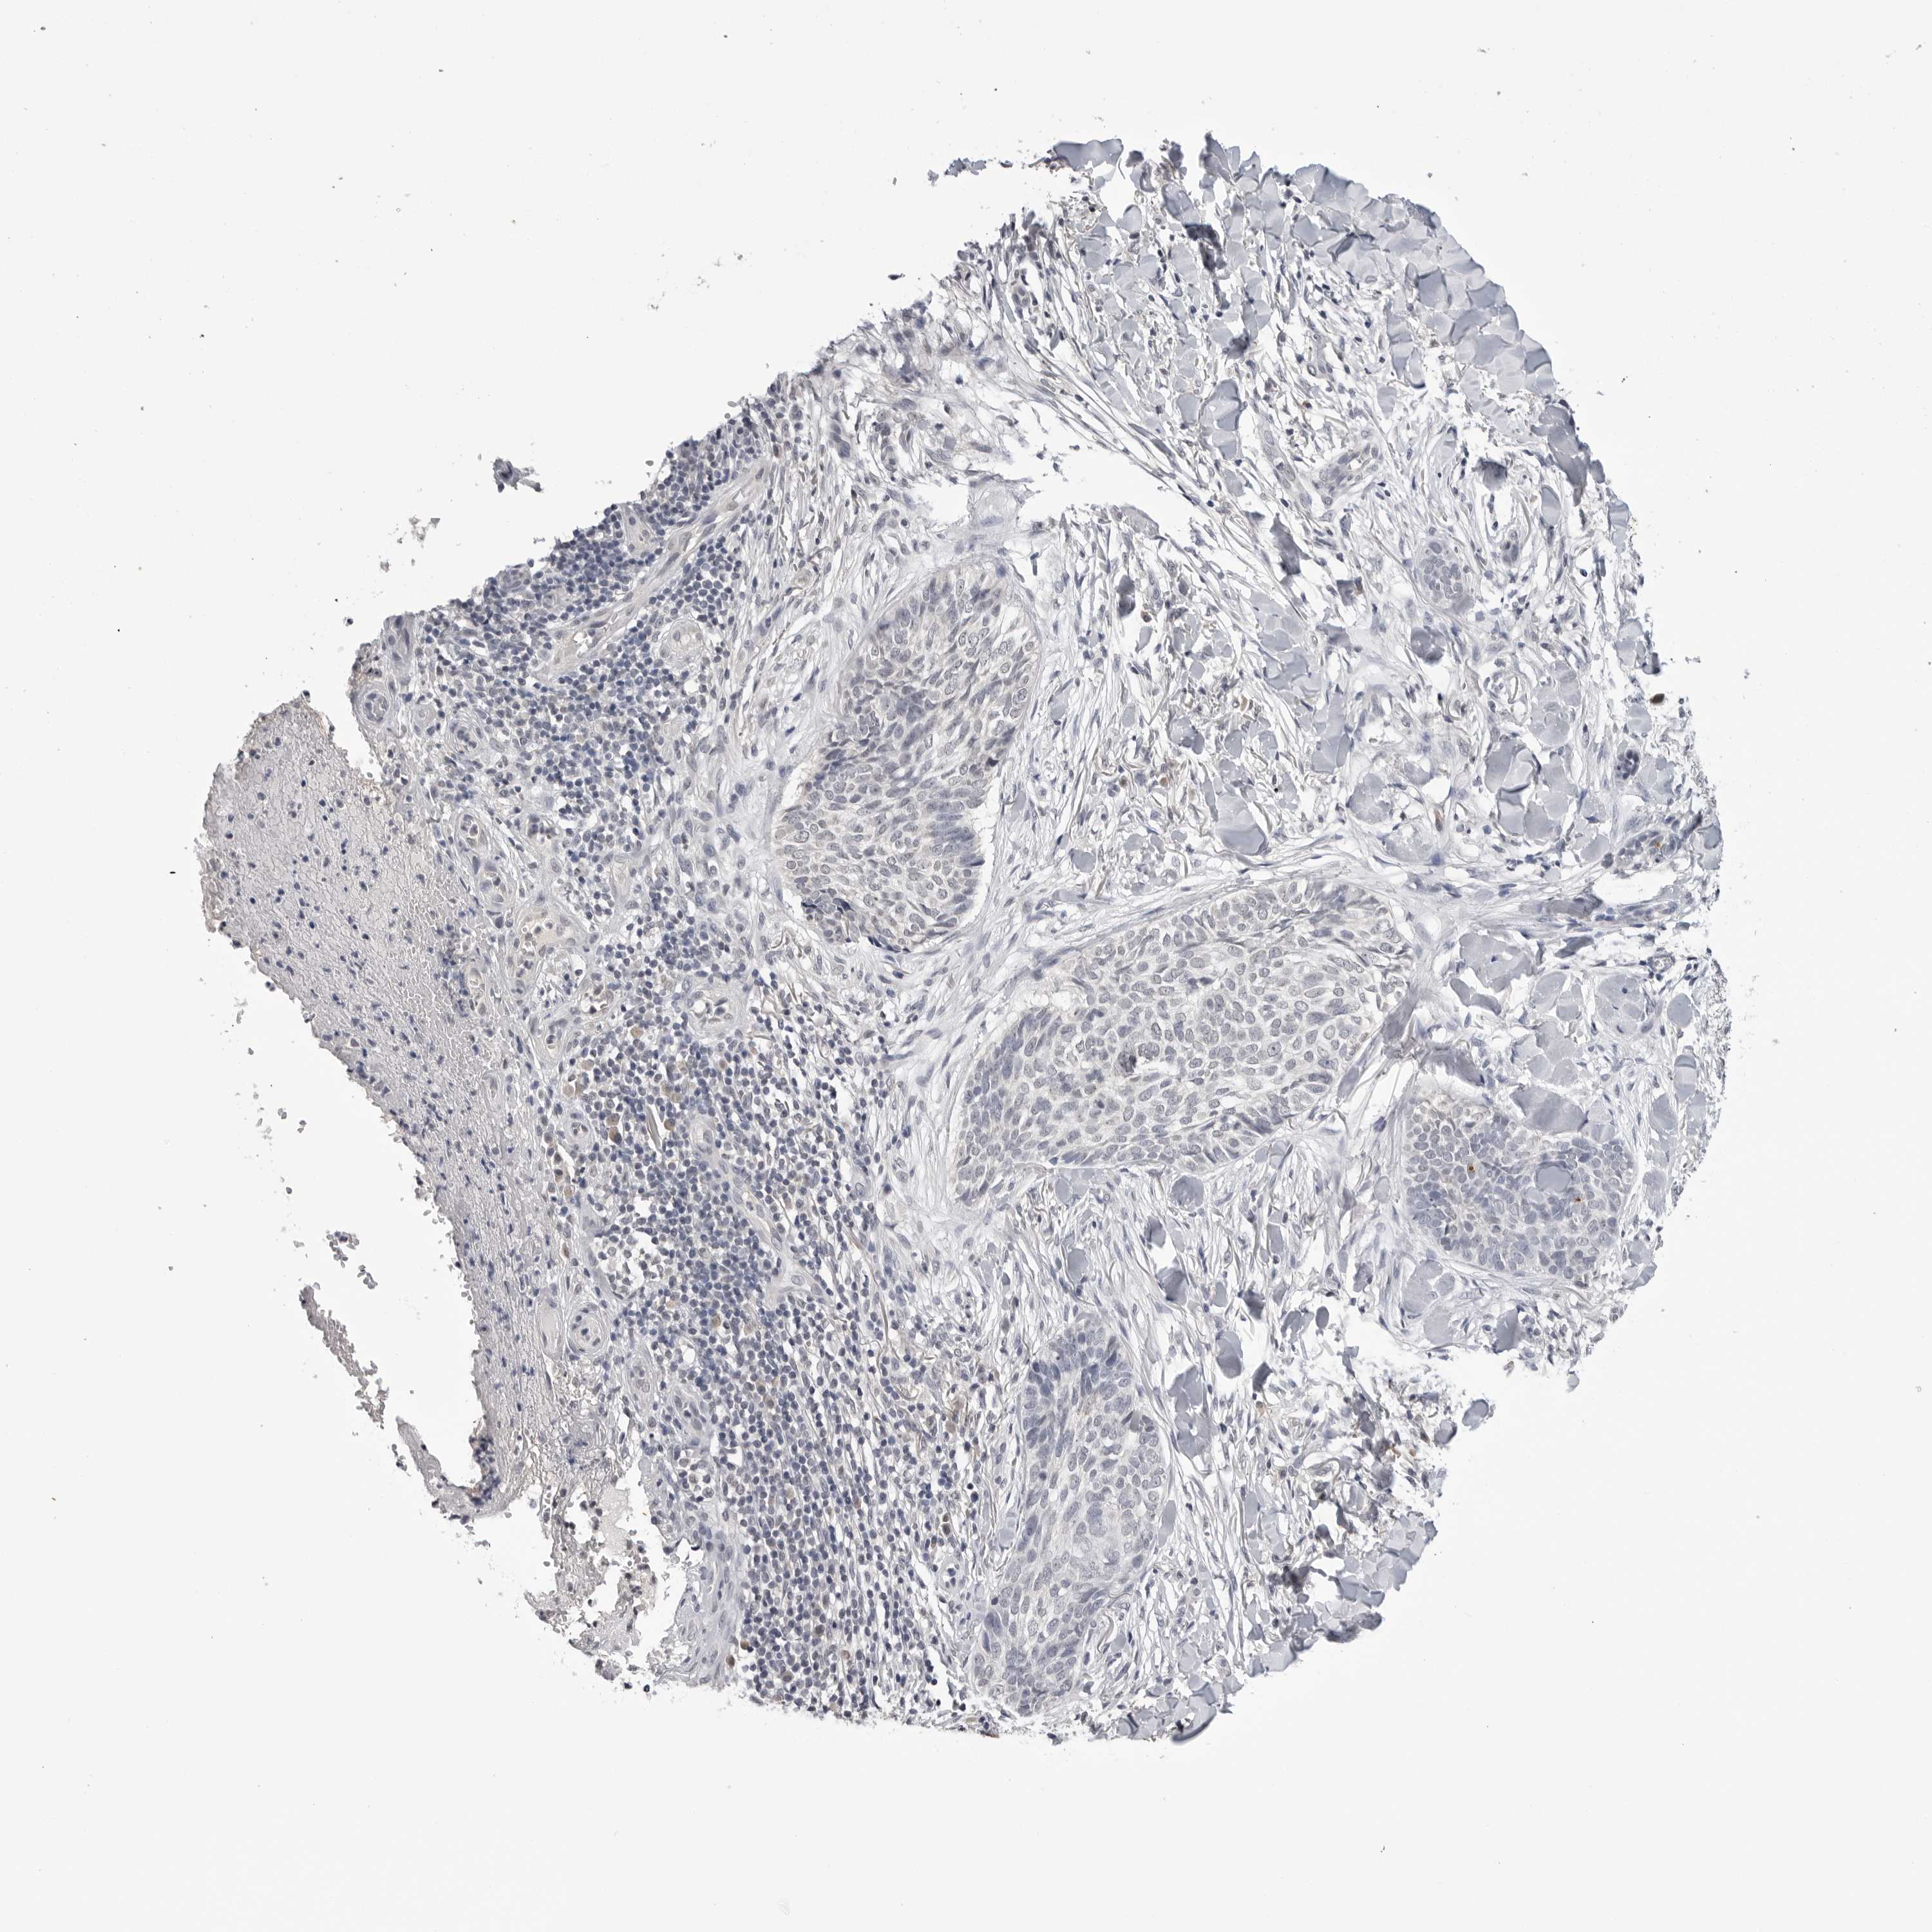

SKIN CANCER - Protein expressioni

A mouse-over function shows sample information and annotation data. Click on an image to view it in a full screen mode. Samples can be filtered based on level of antibody staining by selecting one or several of the following categories: high, medium, low and not detected. The assay and annotation is described here.

Each image is clickable and will lead to virtual microscopy that enables deeper exploration of all samples and also displays staining intensity scores, fraction scores and subcellular localization as well as patient and tissue information for each sample.

Antibody HPA007666

Basal cell carcinoma